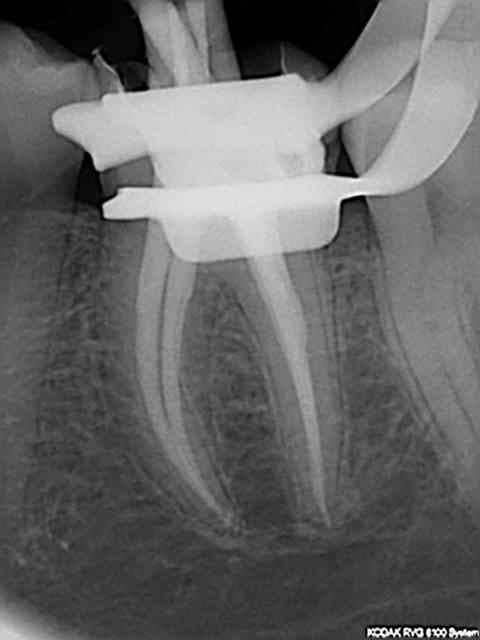

Et une de plus !

R19 vxiysf - Eugenol

R20 kboz6l - Eugenol

01 ukhwbq - Eugenol

C'est pas de la frime hein, mais ca fait plaisir d'avoir trouvé ENFIN une technique rapide et reproductible sans casse. (enfin presque il y a dans le tas un micro morceau de R25 pas loin de l'apex )

Bravo ! Belles images